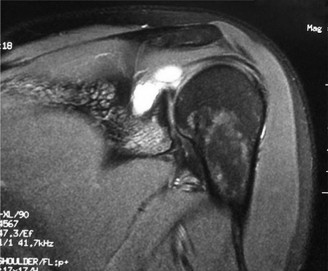

CT arthrograms of the patient’s left shoulder are shown in Figure 2–56. CRP is <3, ESR 45. The patient continues to have pain, so you decide to perform arthroscopic biopsy to obtain tissue cultures. Frozen sections show <5 PMNs per hpf, and Gram stains are all negative.

Figure 2–56

The correct answer is (B). Figure shows contrast under the glenoid component. Given the patient’s normal inflammatory markers and frozen sections combined with continued pain and loosening on CT, infection with P. acnes(an organism that is very difficult to isolate) should be investigated by holding any cultures for at least 2 weeks to see if it will eventually grow. Chocolate agar (Choice C) is mainly used for growing species such as H. influenzae and Neisseria meningitidis not P. acnes. A is incorrect since the patient’s cell count and frozen sections are clearly abnormal, therefore referral to pain clinic would not be appropriate. However, Choice D would be too aggressive an approach given that no organisms have been isolated, frozen sections show <5 PMNs per hpf, and the patient has relatively normal inflammatory markers.